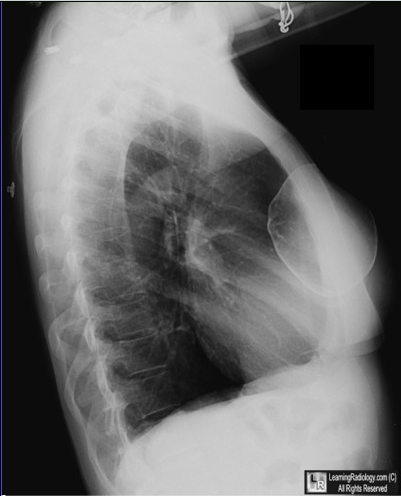

胸部X光片(侧位)